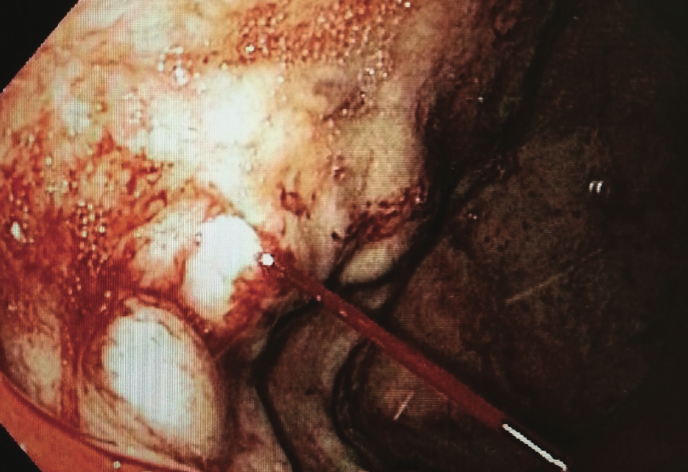

An 87-year-old man presented with a gradual onset of increased abdominal girth of 1 year’s duration. He reported that the associated symptoms had progressed to constant abdominal pain, fatigue, and...